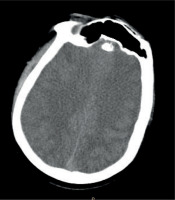

A 24-year-old male patient was admitted to a trauma centre after a motorcycle accident involving a collision with a traffic sign, resulting in a right shoulder injury. Initial evaluation by emergency services showed only paralysis of the right arm; the patient was fully conscious. Upon admission, a whole-body computed tomography (CT) scan was performed, revealing a single fracture of the right collarbone, with no signs of brain injury (Figure 1). Two hours later, the patient fell into a coma, necessitating intubation, sedation, and transfer to the intensive care unit (ICU). A subsequent brain CT scan showed diffuse brain oedema (Figure 2). Intracranial pressure (ICP) was measured at –5 mmHg in the drainage position with the upper body elevated to 30° using a multimodal intracranial probe. The patient remained sedated and ventilated for 48 hours, sustaining stable low ICP levels between –5 and 2 mmHg. Upon cessation of sedation, the patient showed a gradual improvement in consciousness, which was consistent with the changes in ICP levels. Interestingly, higher ICP levels were associated with a better state of consciousness.